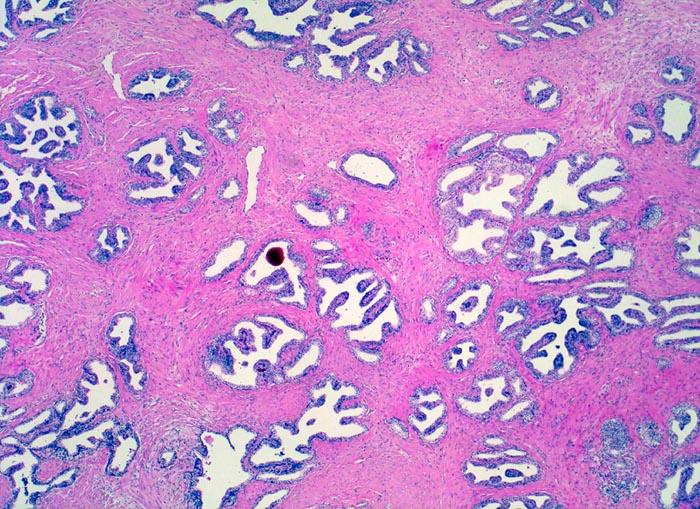

Normale Prostatadrüsen

Normalbefund

Prostata

Genitalorgane, männlich

Das normale Prostataparenchym besteht aus regelmässig angeordneten

Paketen grösserer Drüsen eingebettet in

glatte Muskulatur. Die Drüsen enthalten oft eingedicktes und

verkalktes Sekret.

Histologie

25

60

männlich